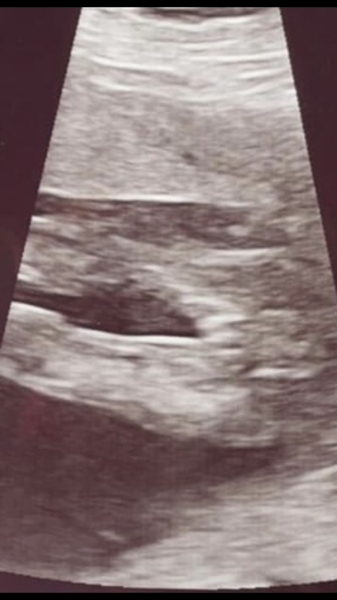

I had a 16 week scan the other day and we did the gender reveal today and I saw the ‘potty shot’. It doesn’t look like the potty shot I have seen before, and looks like it’s more of a side view. I’m just wondering what they have pointed out to be the penis has a line going down the middle and looks a lot bigger than other penis shots I’ve seen!! Is this normal? What is the line down the middle? They didn’t flag up any concerns at the scan!! Has anyone who had boy scans had something similar?